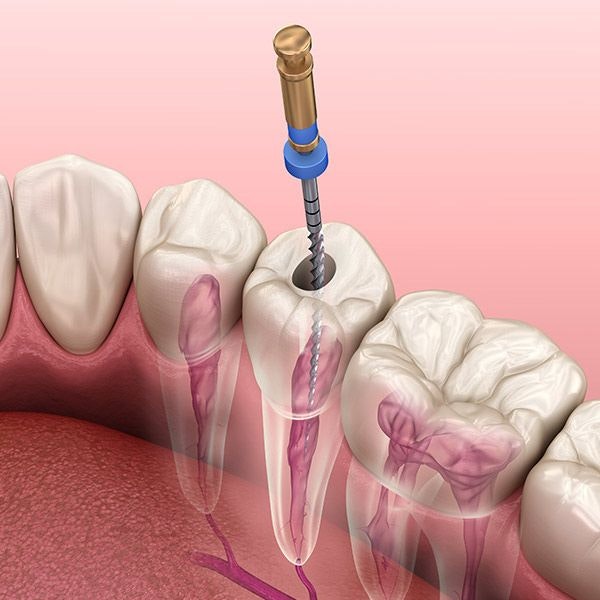

Crowns and Root Canals